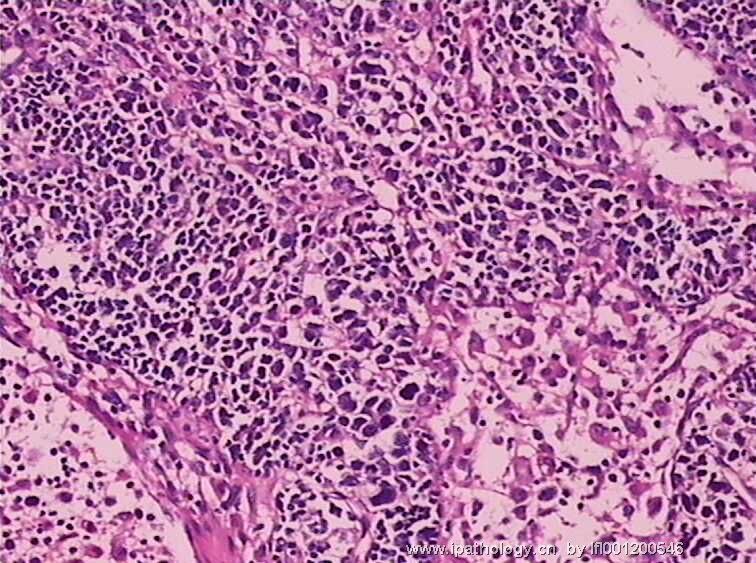

女,45岁,发现颈部多个淋巴结肿大,体查时发现全血细胞减少.取最大的淋巴结送检.

图4

淋巴结结构破坏,有明显异常细胞,结合病史,考虑恶性,淋巴瘤、白血病?不知血片分类怎样?待组化和专家讲解。谢谢!

恶性,考虑淋巴造血系统肿瘤。NHL或白血病。

恶性是肯定,就是要排除转移的恶黑。再考虑原发的非何杰金